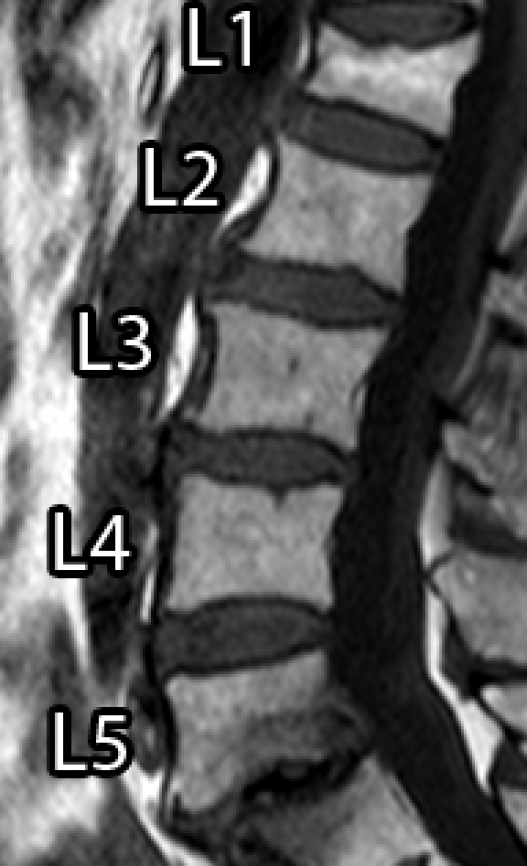

Spinal diseases are quite usual worldwide and can cause significant loss of function and quality of life [1]. A very recurrent disease among older adults is the Vertebral Compression Fracture (VCF), which, in general, is caused by osteoporosis (benign) or bone metastasis (malignant) [2, 3, 4]. In general, VCFs are early detected or diagnosed based on shape or texture using Magnetic Resonance Imaging (MRI) [5, 6, 3, 7]. Usually, a specialist manually segments the Region of Interest (ROI) to aid the diagnose, which can be time consuming and prone to errors, due to inter and intra-subject variability and the subjective judgment that is employed [8].

However, it incorporates expert knowledge gained over several years. Figure 1 shows an example of manual segmentation over five lumbar vertebral bodies (L1-L5).

| (a) Original image | (b) Ground-truth |